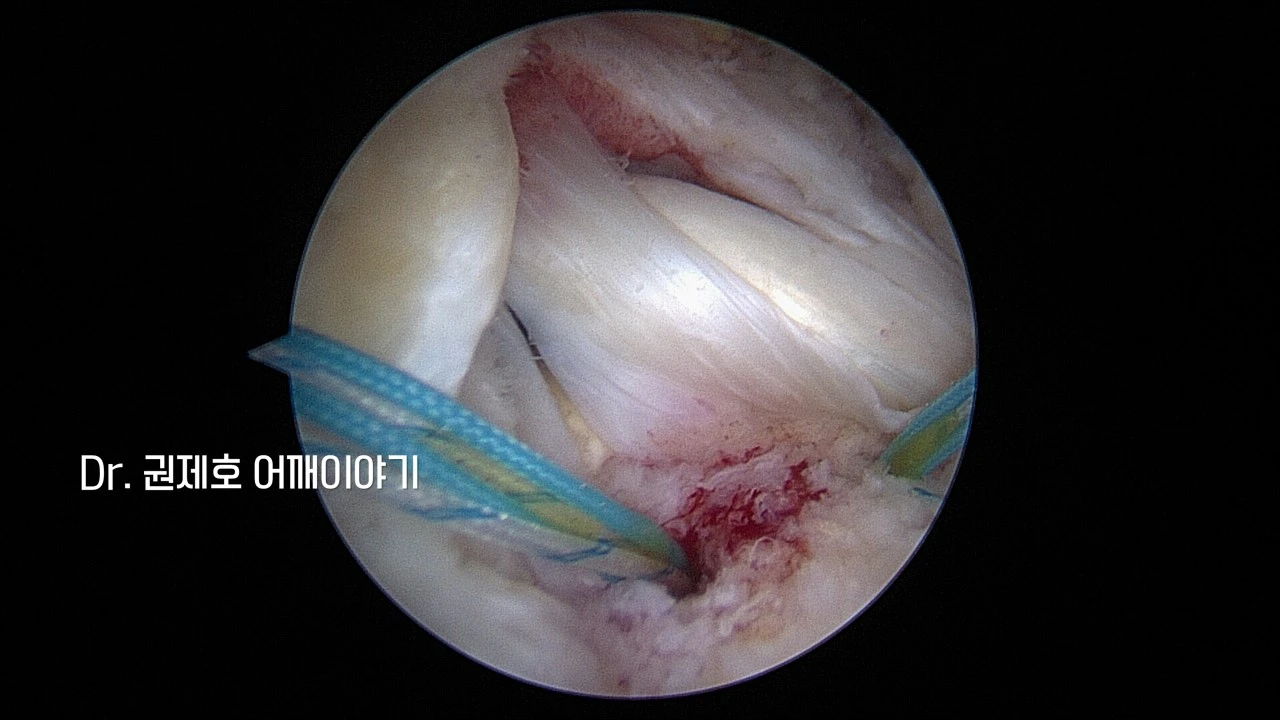

어떤 모양으로 찢어졌고, 헤졌는지를 파악한 후 어느 방향으로 봉합 수술할지 결정이 되고 나면, 이제 봉합사를 삽입하여 본격적으로 봉합수술을 진행한다. 위 사진에서는 봉합사를 뼈에 심고 나서 실들이 나온 모습들이다.

이렇게 인대 끊어짐이 있은 후 헤지고, 말려버리면, 단순 봉합은 힘들다. 따라서 시간이 조금 더 걸릴지언정, 이중으로 봉합 수술하는 것이 더 좋은 결과를 기대할 수 있다. 이중 봉합을 어깨관절경 회전근개 브리지 봉합수술이라고 한다.